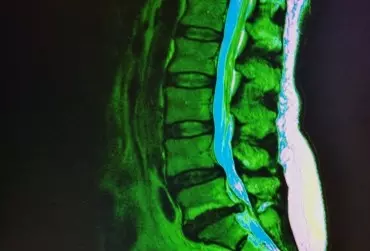

Diagnostyka różnicowa odcinka lędźwiowego kręgosłupa i stawu krzyżowo-biodrowego - część 2

Dolegliwości bólowe w okolicach kręgosłupa lędźwiowego i stawu krzyżowo-biodrowego, które najczęściej stanowią powód zgłoszenia się pacjenta po pomoc, mogą być spowodowane bardzo różnymi przyczynami, poczynając od wad postawy, poprzez dysfunkcje somatyczne, trzewne, patologie strukturalne, urazy, zmiany zwyrodnieniowe i przeciążeniowe, choroby zapalne, na chorobach nowotworowych kończąc. Odpowiednio przeprowadzona diagnostyka umożliwia prawidłowe rozpoznanie, które jest niezbędne do wdrożenia skutecznego leczenia i rehabilitacji.